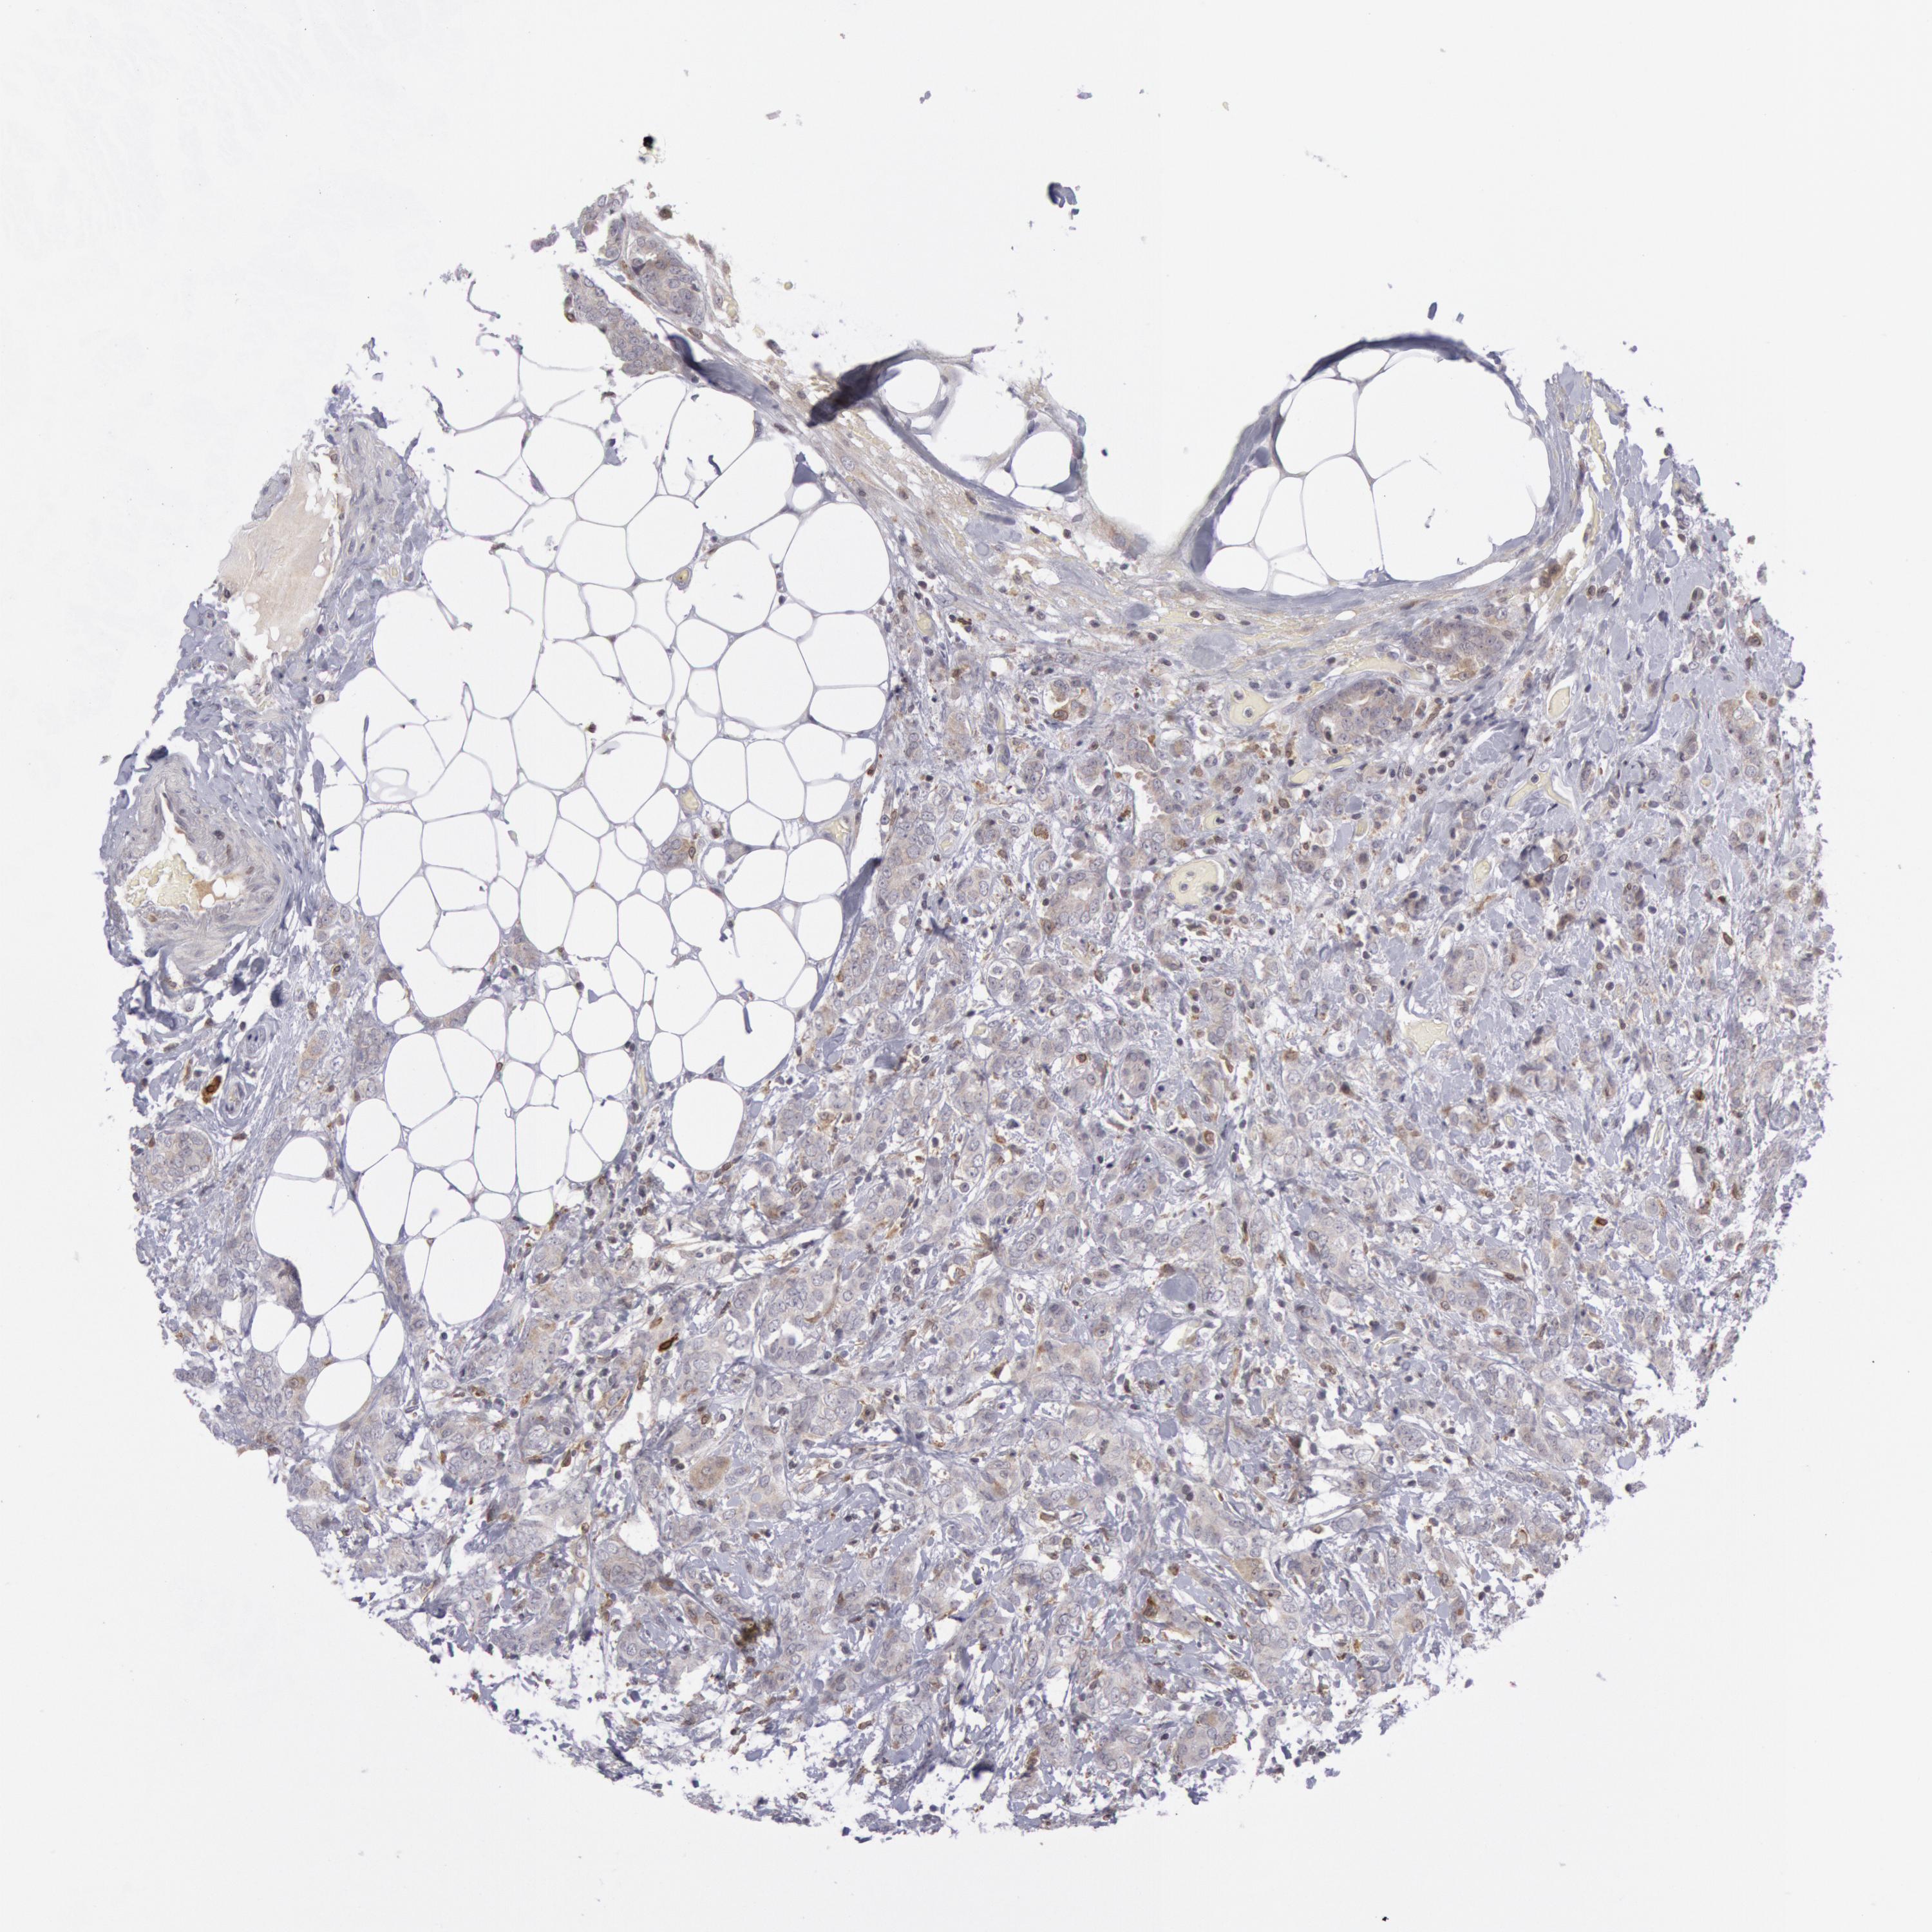

CANCER BREAST CANCER Show tissue menu

BRCA TCGA BRCA VALIDATION PROTEIN EXPRESSION

ANTIBODIES

AND

VALIDATION